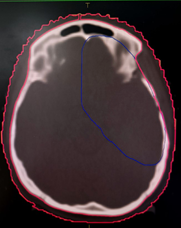

to the level of the foramen magnum (6) as depicted in Figure 1 given below.

Figure 1. shows scalp contours in axial, coronal,

and sagittal planes.